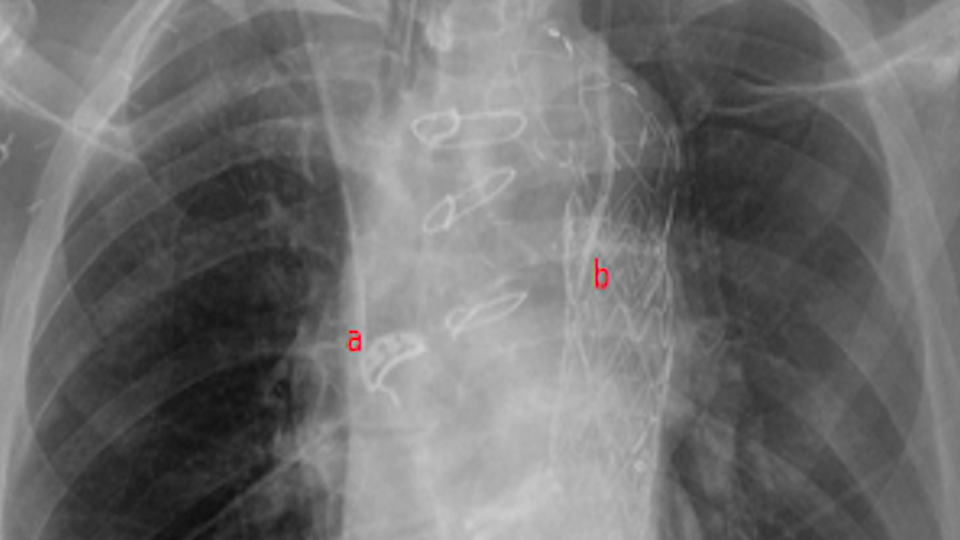

De l’importance du contrôle radiographique post-cathéter veineux central : à la découverte des variantes anatomiques !

Cathéter veineux centraux et variantes anatomiques vasculaires

cathéter intra vasculaire, Radiographie de thorax, variantes anatomiques, réanimation